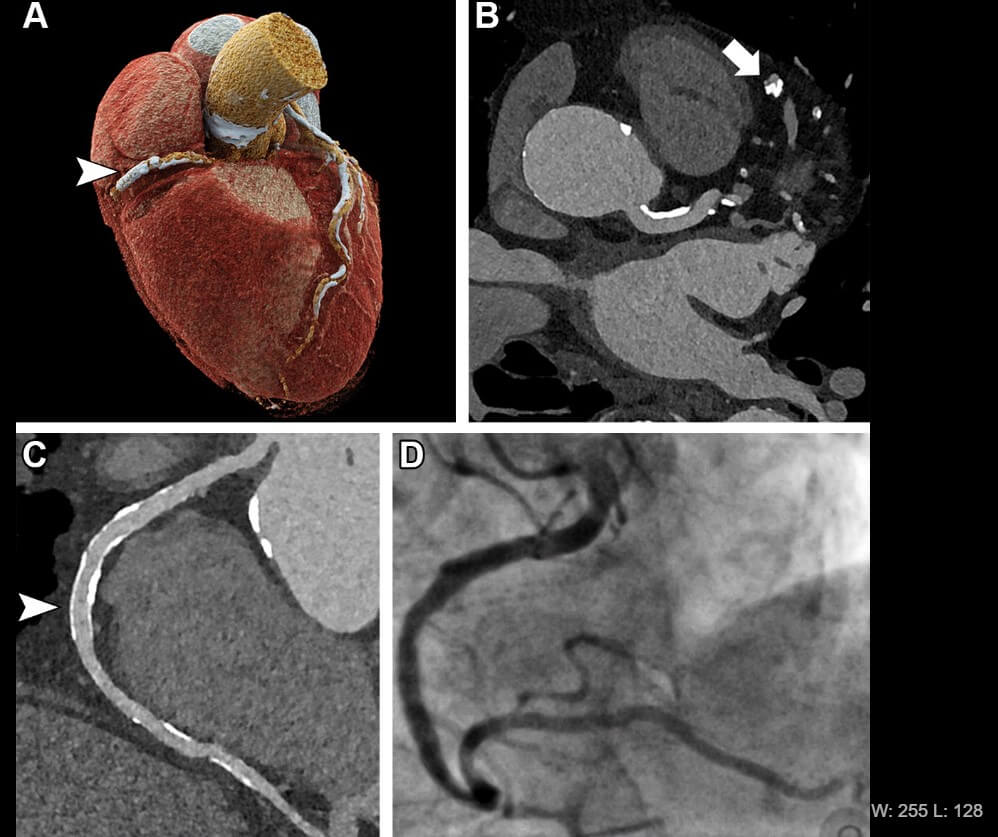

Technology used today — coronary computed tomography angiography (CCTA) — is quite effective at ruling out coronary artery disease in patients with low or intermediate risk. However, screening high-risk individuals can be challenging due to a high prevalence of calcifications, which can often appear more extensive than they truly are and result in false positives.

This innovative tool employs a photon-counting detector. In the first comprehensive study of its kind, researchers compared its diagnostic accuracy with the reference standard of invasive coronary angiography (ICA) in 68 patients suffering from severe aortic valve stenosis, a common but serious valve disease that impedes or blocks blood flow from the heart.

The UHR-CCTA proved to be highly sensitive and specific for coronary artery disease detection, achieving a median overall image quality score of 1.5 on the 5-point Likert scale (where one represents excellent and five signifies non-diagnostic). Approximately 80% of segments were rated as good or excellent, indicating that this technique could soon be available to high-risk patients.